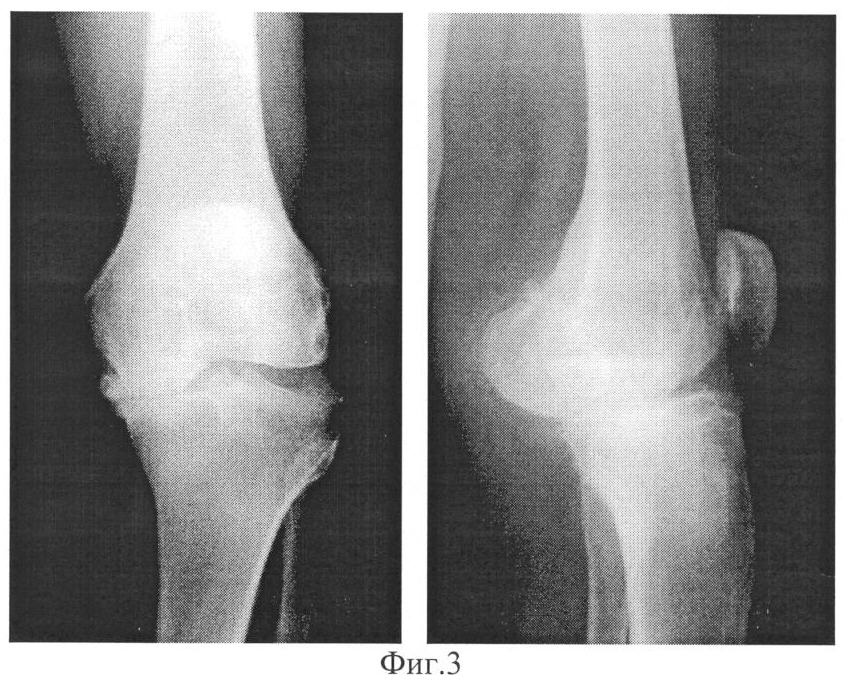

фиг.1 иллюстрирует рентгенограммы правого коленного сустава больной В., 72 лет в двух проекциях при компенсированной стадии остеоартроза;

На рентгенограммах правого коленного сустава признаки остеоартроза коленного сустава: заострение межмыщелковых возвышений большеберцовой кости, усиление субхондрального склероза в суставных отделах (фиг.1).

С помощью предлагаемого способа диагностики произведено измерение внутрикостного давления в костно-мозговой полости правой большеберцовой кости, которое составило 10 мм рт.ст.

При сопоставлении величины внутрикостного давления с данными таблицы 1 установлено, что она соответствует компенсированной стадии процесса.